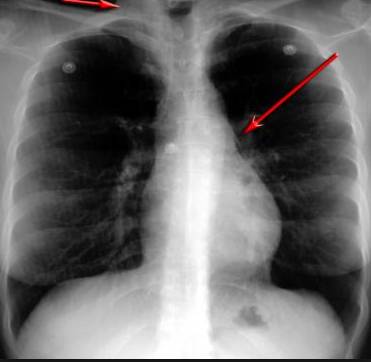

并且,因?yàn)楹粑到y(tǒng)結(jié)構(gòu)復(fù)雜,在體檢時(shí)醫(yī)生很難通過一種檢測手段,判定早期患者的病情。

使用這臺(tái)掃描儀,將直接把器官變成3D圖形!細(xì)微的毛細(xì)血管,幾毫米大的肺泡和支氣管,都將能看的一清二楚!

你的每一個(gè)氣泡,每一段支氣管,哪兒有病變都清清楚楚的將展示在醫(yī)生面前!

也就是說在一切都還沒開始惡化前,把這些有問題的器官組織都暴露的一清二楚:

這臺(tái)儀器不僅僅是一臺(tái)能拯救幾百萬條生命的高清掃描儀,它更是一場開天辟地的技術(shù)革新!因?yàn)樗粌H能幫醫(yī)生看到肺病的結(jié)構(gòu)圖,

還能看到器官是如何運(yùn)動(dòng)的!

空氣是如何進(jìn)入到肺部,氧氣是如何到血液,任何微小的變化都將曝露在醫(yī)生面前!更清晰的圖像,更細(xì)節(jié)的變化!

不同于CT掃描,需要從同一角度,拍下無數(shù)張器官二維圖,從而搭建3D器官結(jié)構(gòu)圖那般費(fèi)時(shí)費(fèi)力。

4D掃描儀將直接從不同角度,同時(shí)對(duì)人體器官進(jìn)行掃描,然后通過計(jì)算機(jī)算法進(jìn)行快速成像。CT需要花幾小時(shí)才能完成的工作,

4D掃描將在幾秒內(nèi)完成!

當(dāng)大家還在為B超、X光、CT哪個(gè)輻射更少而爭論不休時(shí),這臺(tái)新機(jī)器已經(jīng)比現(xiàn)有掃描儀少20%的輻射

沒有這項(xiàng)新技術(shù),醫(yī)生在做體檢的時(shí)候,很難通過一種測試斷定一個(gè)人是否有呼吸系統(tǒng)疾病。

可是現(xiàn)在他們不但能看到整個(gè)肺部的3維結(jié)構(gòu)圖。還能看到空氣進(jìn)入人體后的所有微小變動(dòng)!